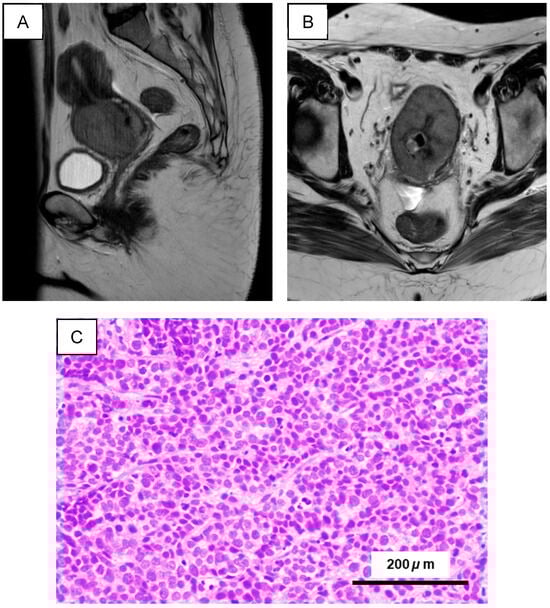

Integrated Molecular and Functional Characterization of Cervical Small-Cell Neuroendocrine Carcinoma Using a 3D Organoid Model

by Hasibul Islam Sohel, Umme Farzana Zahan, Masako Ishikawa, Kosuke Kanno, Hitomi Yamashita, Kentaro Nakayama and Satoru Kyo

Int. J. Mol. Sci. 2026, 27(5), 2393; https://doi.org/10.3390/ijms27052393 (registering DOI) - 4 Mar 2026

Cervical small-cell neuroendocrine carcinoma (SCNEC) is a rare cervical cancer with high metastatic potential and is frequently associated with high-risk human papillomavirus (HPV) infection. Because of its low incidence, SCNEC remains understudied and treatment options are limited, posing major therapeutic challenges. This study aimed to characterize SCNEC at the molecular and functional levels to support more informed therapeutic strategies. Organoids and spheroids were generated from a cervical SCNEC biopsy, and a matched organoid-derived xenograft was established in immunodeficient mice. Model fidelity was evaluated by histopathology and immunohistochemistry. HPV status was assessed by p16 immunostaining and HPV18 PCR, and viral–host integration sites were inferred using whole-exome sequencing (WES) junction reads. WES was also used to compare shared somatic variants and copy-number alterations across the patient tumor, organoid, and xenograft. Drug responses were assessed in organoids and spheroids following exposure to a panel of chemotherapeutic agents and a targeted inhibitor. Organoids exhibited robust growth, morphologic maturation, and efficient recovery after cryopreservation. The organoids and matched xenografts faithfully recapitulated SCNEC, with preserved neuroendocrine differentiation (CD56, synaptophysin, and NSE positivity), a high Ki-67 proliferative index (>80%), and strong p16 expression. HPV18 status was conserved across the primary tumor, organoids, and xenografts, with an integration site at chr8 (8q24.21) associated with increased MYC expression. Whole exome sequencing (WES) revealed strong cross-model concordance, including 26 shared somatic variants with a canonical PIK3CA hotspot mutation (p.E542K) and conserved oncogenic copy-number gains of PIK3CA, TERT, and MYC, as well as copy number loss of TP53. Functional assays showed dose-dependent loss of viability following exposure to conventional cytotoxic agents or an mTOR pathway inhibitor. This study presents the first integrated molecular and functional analyses of patient tumors and matched organoid and xenograft models in cervical SCNEC. These models offer robust resources for mechanistic studies and may enable precision therapeutic strategies for this rare malignancy. Full article

Figure 1